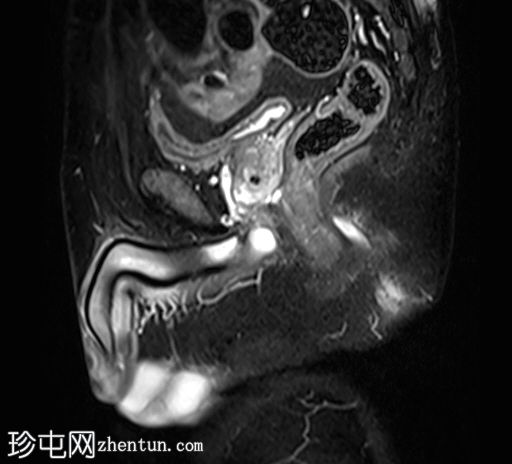

矢状位

T1时间

位于5点钟和6点钟位置之间,在STIR和T2加权图像上呈高信号。

瘘管起源于括约肌间平面附近,穿过肛门内外括约肌,并延伸至左侧坐骨肛门窝。瘘管内充满液体信号,周围有轻微水肿。肛提肌上方未观察到颅骨延伸。

根据圣詹姆斯大学医院的磁共振分类系统,该病例被归类为III级左侧肛周经括约肌瘘,左侧坐骨肛门窝可见炎症改变。